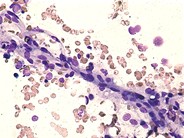

Bone marrow vessel - 1.

Category: Laboratory Hematology > Normal and reactive bone marow

Vessels can sometimes be seen as part of bone marrow stromal elements. The enothelial cells, which make up the walls of the vessel, have a characteristic elongated "spindle" appearance.